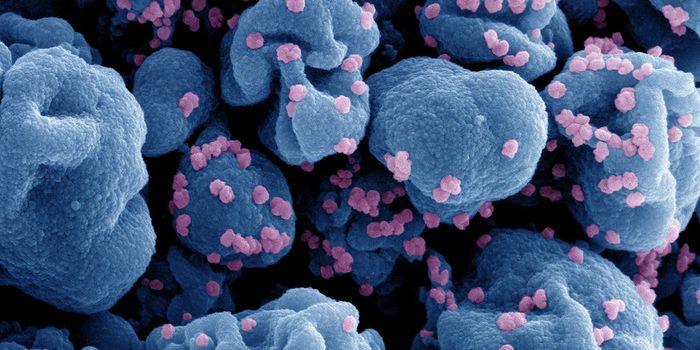

FEB 13, 2025ImmunologyImmunotherapy has changed the way physicians treat cancer patients. This approach to therapy targets the immune system t ...

DEC 19, 2024ImmunologyImmunotherapy has transformed the field of cancer medicine. It has extended survival rates, reduced toxicity, and, in so ...

DEC 19, 2024ImmunologyImmune checkpoint inhibitors (ICIs) have shown significant promise in treating tumors. Immune checkpoint inhibitors are ...

DEC 12, 2024ImmunologyImmunotherapy has changed the way physicians treat patients and has improved standard of care for many different tumors. ...

DEC 09, 2024CancerCancer cells have evolved sophisticated strategies to evade the immune system, prolonging their survival and growth.&nbs ...